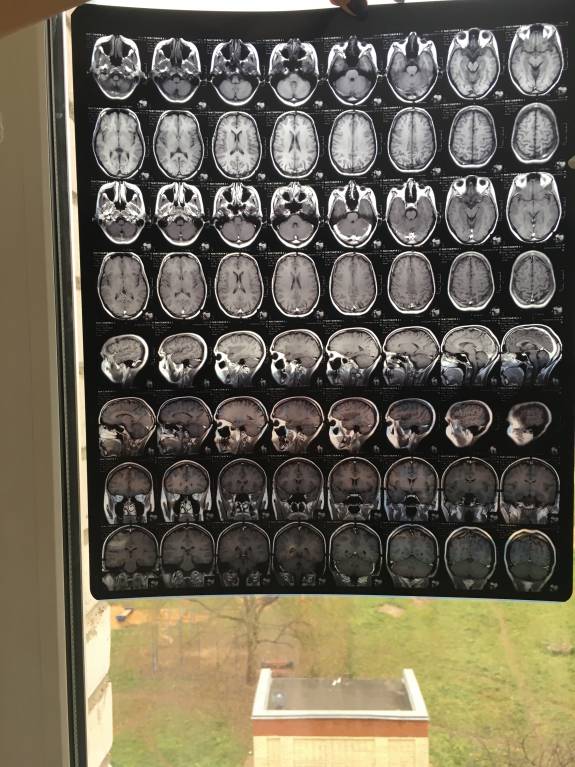

Общалась с Вами по телефону неделю назад, после того как мне на МРТ продиагностиргвали кисту шишковидной железы головного мозга.

Отправляю Вам снимки МРТ, Очень надеюсь на вообще мнения о причине возникновения кисты.

Снимок головы с контрастом

Здравствуйте, Евгения. Пленки мрт желательно смотреть (зная и видя пациента) на специальном экране, в полном размере. Отсюда можно увидеть, что они есть. Не более. Вполне логично, если врачи сделают заключение по месту проведения исследования. Если останутся сомнения, проконсультируйтесь в другой клинике, только отвезите сами снимки.